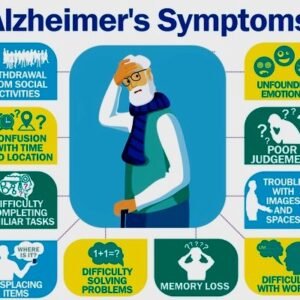

Alzheimer’s Disease (Early Stage)

$0.00 Add to cart -